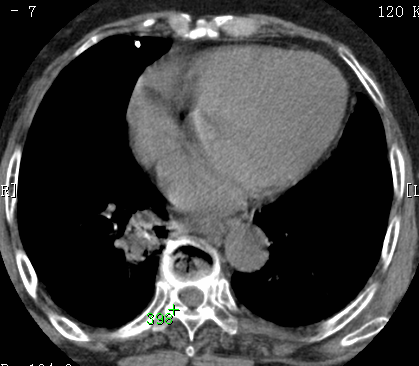

标题: CT26680:肺部右下肺静脉干结节的界定 [打印本页]

标题: CT26680:肺部右下肺静脉干结节的界定

经追查说有支扩咯血病史,但不确定

考虑1、周围型肺癌,2肺静脉畸形,前者可能大,建议增强检查。

考虑1、周围型肺癌,2肺静脉畸形,前者可能大,建议增强检查。支持!

不排除右肺下叶周围型肺癌可能。

中心型肺癌,纤支镜可帮助明确。